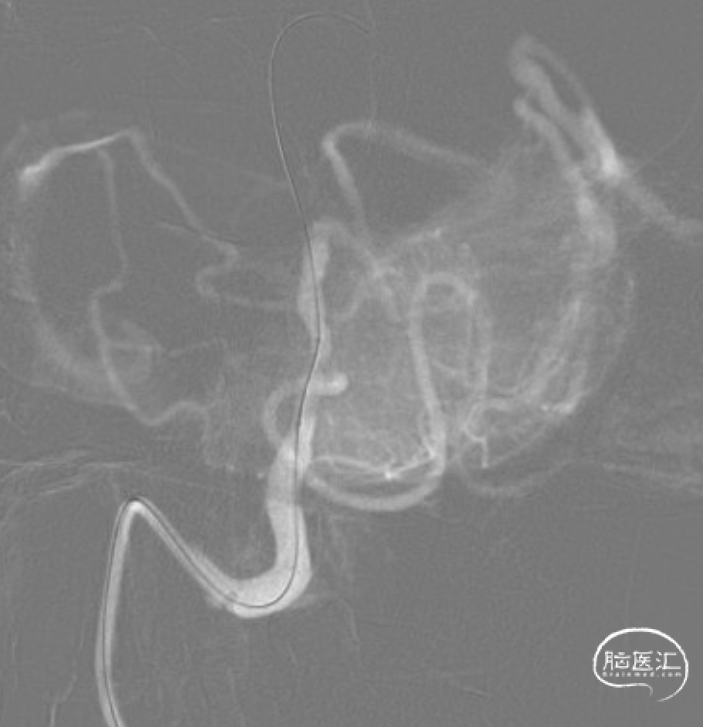

远端通路导管到位。

微导丝通过病变。

赛诺Neuro LPS®颅内球囊扩张导管 2.75*15mm输送至病变位置。

缓慢扩张至命名压3atm。

球扩后造影观察。

赛诺NOVA®颅内药物洗脱支架 2.75*12mm输送至病变段。

10atm压力释放赛诺NOVA®颅内药物洗脱支架。

术后造影:RV4段狭窄较前明显改善。